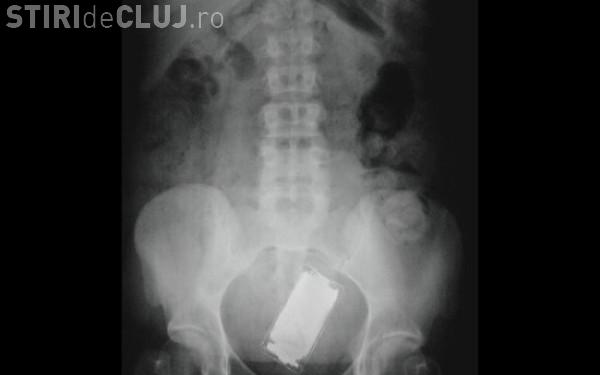

Un pacient din SUA i-a socat putin pe medici cand s-a prezentat in camera de garda cu un iPod introdus in anus. Cazul a fost rezolvat de medici, anunta huffingtonpost.com.